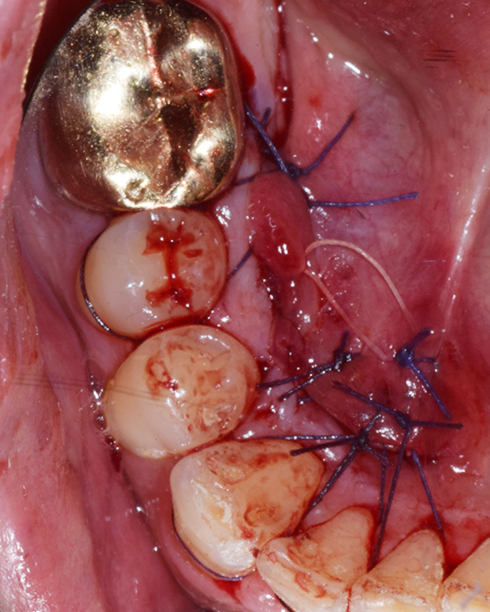

A surgical procedure to remove tori

Tori do not have to be removed in most cases. Tori are removed to accommodate upper or lower dentures.